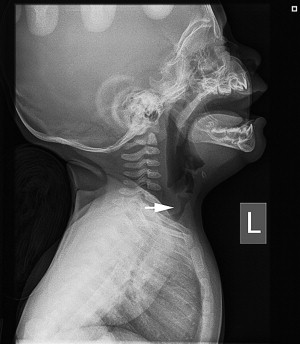

At the initial presentation of a child with stridor, plain films of the airway will show a tapered subglottic airway and a subglottic mass with a subglottic hemangioma and are very useful for assessing the subglottis ( Fig. 1 ). This is to be differentiated from subglottic stenosis or subglottic cysts. With these two pathologies, there is usually a history of intubation except with congenital subglottic stenosis, which is quite rare.

Less common sites affecting the airway include postcricoid, tracheal, mediastinal, thoracic, and esophageal. They may stain the posterior trachealis muscle (see Fig. 4 ). Airway symptoms include biphasic stridor and recurrent croup. Diagnosis may be suggested by history and lack of another cause of subglottic stenosis, such as prolonged intubation. Plain neck films may suggest the diagnosis.